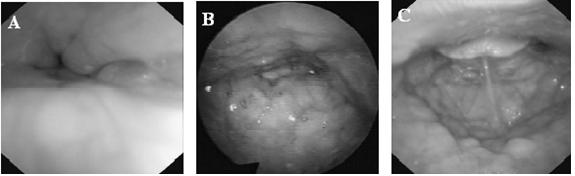

Η κατάταξη VOTE χρησιμοποιείται για την έκφραση των αποτελεσμάτων της Ε.Φ.Υ. με κοινά αποδεκτό τρόπο. Αντιπροσωπεύει μια κοινή γλώσσα που περιγράφει τους τύπους της απόφραξης και μπορεί να καθορίσει τις θεραπευτικές παρεμβάσεις.

Έτσι σύμφωνα με την κατάταξη VOTE καθορίζουμε: i) το σημείο της απόφραξης (Μαλακή υπερώα – Velum, στοματοφάρυγγας – Oropharynx, βάση της γλώσσας – Tongue base, επιγλωττίδα – Epiglottis), ii) το βαθμό της απόφραξης (αμελητέος, μερική απόφραξη, πλήρης απόφραξη), και iii) τον τύπο της απόφραξης (προσθι-οπίσθιος, συγκεντρικός, εκ των πλαγίων).